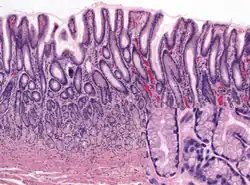

Histology of normal fundic mucosa. Fundic glands are simple, branched tubular glands that extend from the bottom of the gastric pits to the muscularis mucosae; the more distinctive cells are parietal cells. H&E stain.

Within the body and fundus of the stomach lie the fundic glands. In general, these glands are lined by column-shaped cells that secrete a protective layer of mucus and bicarbonate. Additional cells present include parietal cells that secrete hydrochloric acid and intrinsic factor, chief cells that secrete pepsinogen (this is a precursor to pepsin- the highly acidic environment converts the pepsinogen to pepsin), and neuroendocrine cells that secrete serotonin.[25]